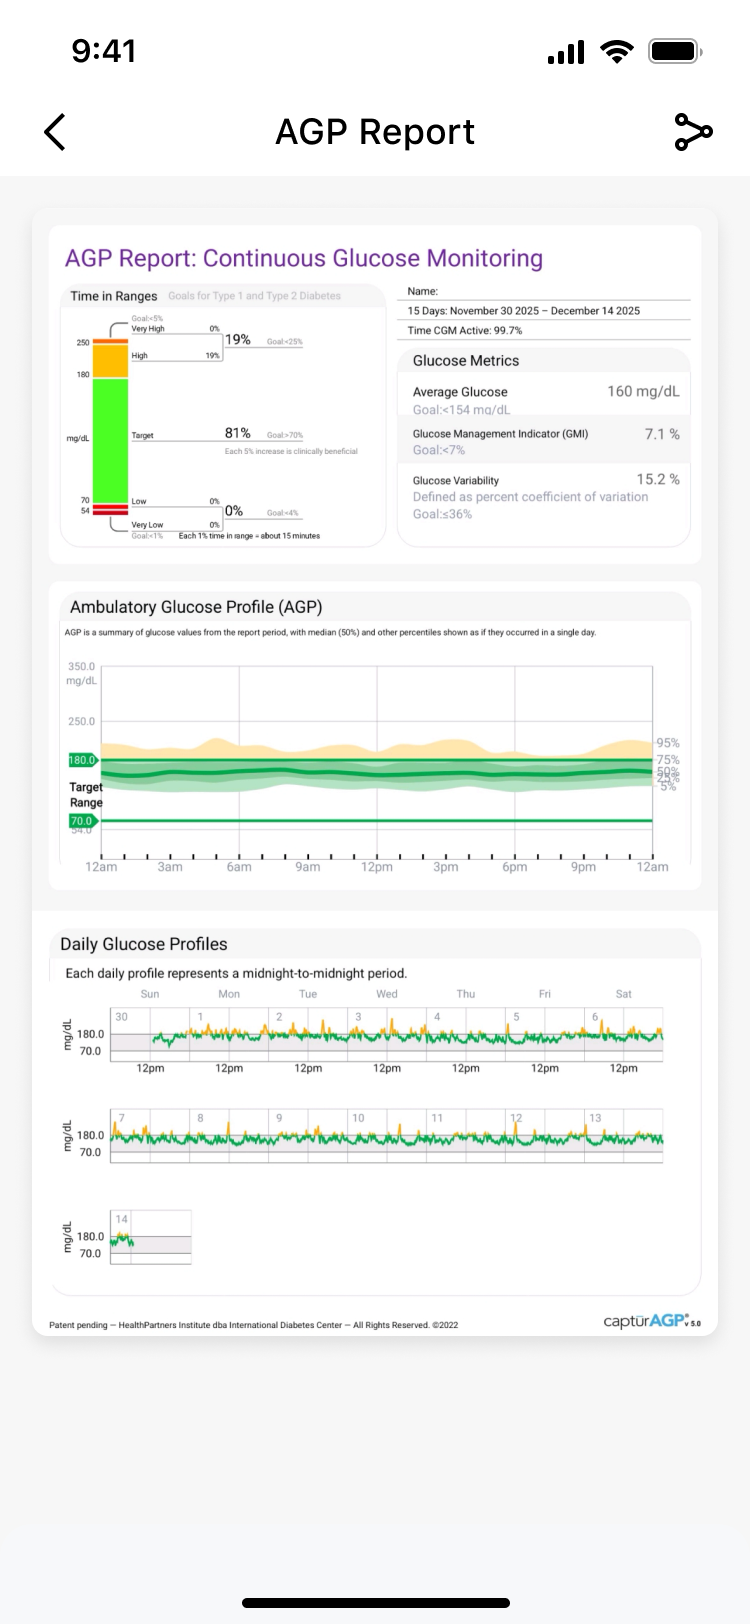

Turn your continuous glucose data into actionable insights. Unlock how your diet, exercise, and sleep personally affect you. Easily monitor your levels and generate professional reports anytime, anywhere. This is health management, simplified—putting you in control of your future.